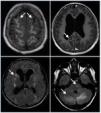

El hallazgo radiológico característico es la presencia en la resonancia magnética de lesiones hiperintensas en las secuencias T2 y FLAIR, frecuentemente bilaterales y localizadas en las regiones cerebrales posteriores, que se corresponden con zonas de edema vasogénico (fig. 2).

Figura 2. Imagen radiológica del síndrome de encefalopatía posterior reversible (SEPR).

Se conoce poco de la fisiopatología del SEPR. La teoría más aceptada, sobre todo en los casos asociados a hipertensión, es la pérdida de la autorregulación cerebral, que conduce a la aparición de edema vasogénico. Su característica principal es la reversibilidad, tanto de la clínica como de las lesiones cerebrales, siempre que se realice un diagnóstico precoz y un tratamiento adecuado.